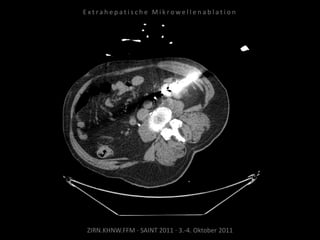

Ablation am 25.03.2010:

1 Nadelposition, 45 W, 7 Min.

Während der Ablation werden

Harnleiter, Harnblase und Rektum

zwecks Hitzeableitung gespült zur

Vermeidung thermischer Schäden.